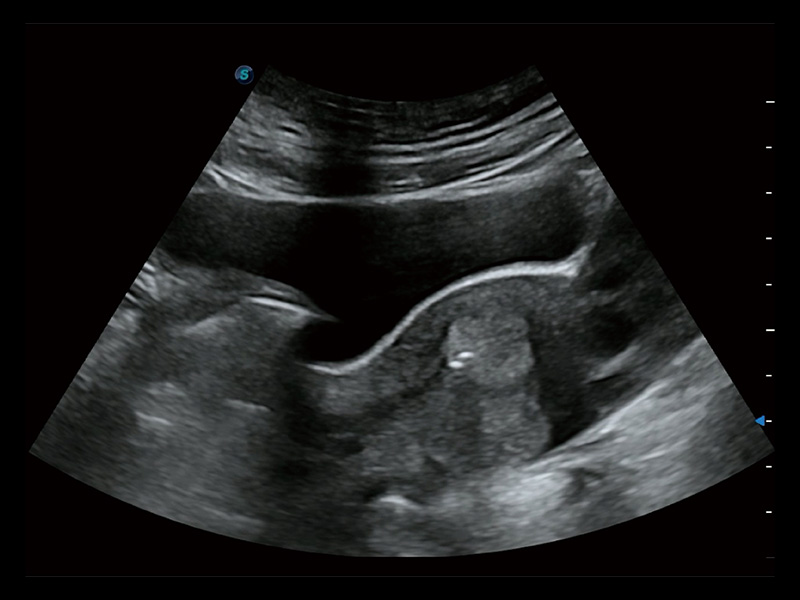

采用弯柄探头替代窥器下叶,巧妙实现了实时超声监控下的单人手术操作。探头频率高、图像清晰,不受肥胖影响,使得手术过程中无需充盈膀胱,即可有效进行胚胎移植、减胎手术的精准操作。

超声引导下胚胎移植